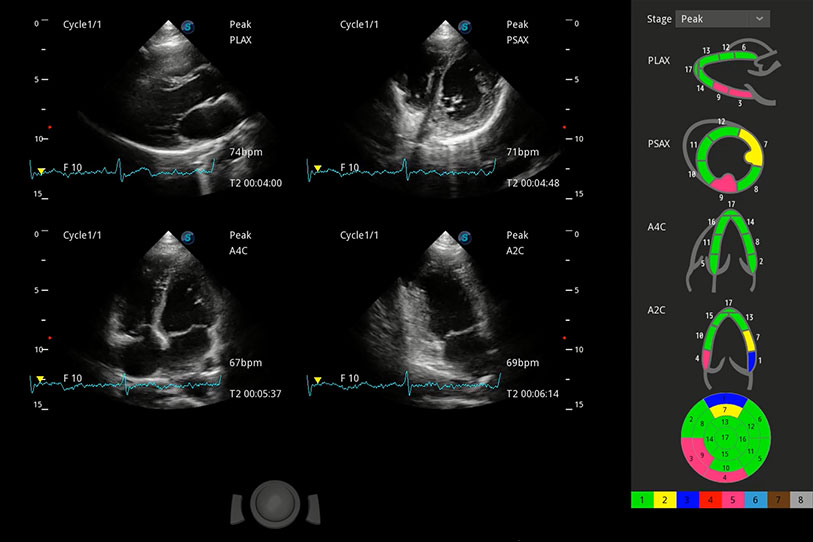

能够基于左心室壁追踪和辛普森法,自动计算射血分数,支持多个可移动点描迹,与手动测量相比,极大节省了动物医生的时间和精力。

具备多种协议可选,同时支持17阶段划分法和专业的SE报告。

实时用颜色表示心肌组织运动,观察和定量组织的运动情况,对快速检测与评估心肌的灌注和活性、电传导及心肌收缩和舒张功能等均能提供重要的诊断信息。